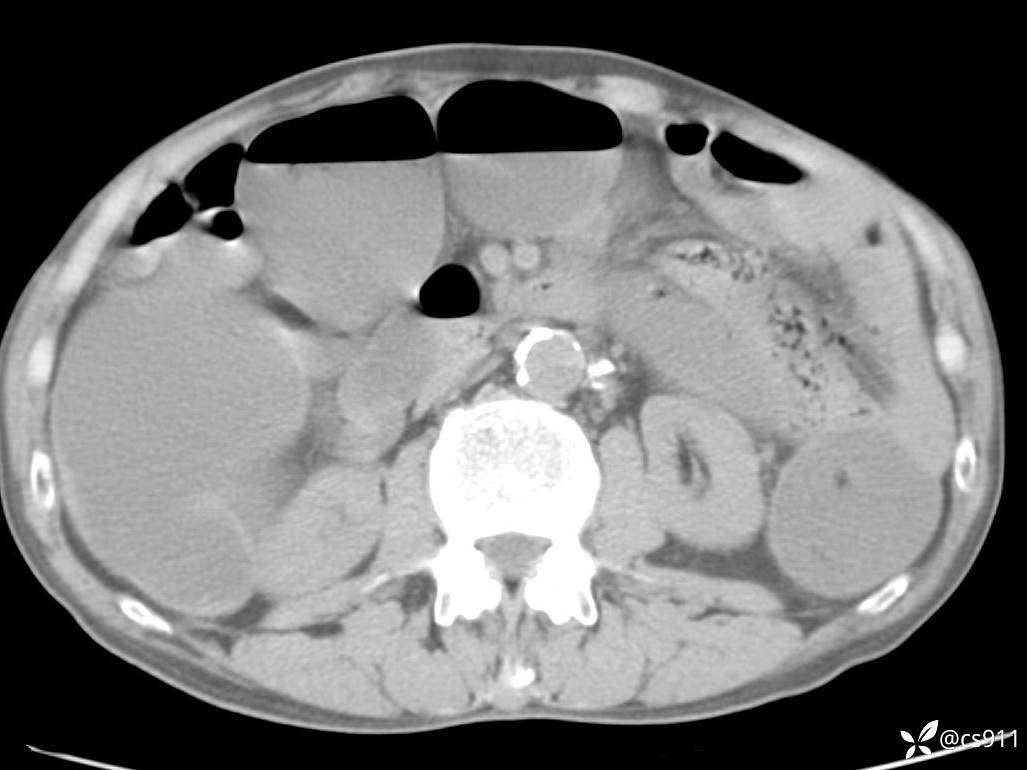

急腹症之急诊CT,原因?答案公布

男,77岁,腹痛、腹胀伴恶心呕吐1天。呕吐胃内容物,非喷射性呕吐,有咖啡色样胃内容物,诉有胃穿孔病史。查体:全腹平,下腹部压痛,全腹无反跳痛,叩诊呈浊音,移动性浊音阴性,肠鸣音减弱,1-2次/分。肛检:直肠未扪及明显肿物,可触及大量粪块。

血淀粉酶(AMY) HH 1859 U/L 35-135

癌胚抗原(CEA) H 27.44 ng/ml 0-5